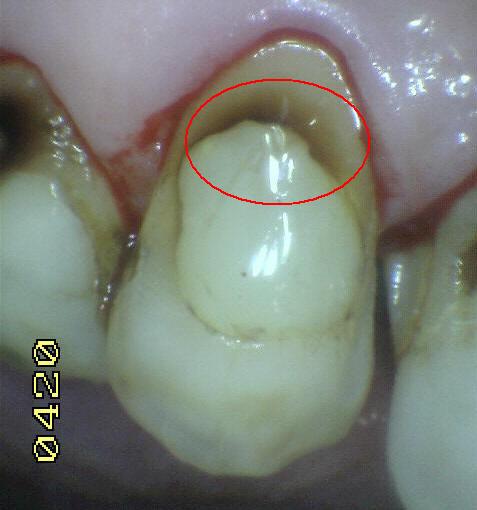

Código 1(Caries

Inicial): Primer cambio

visible en el esmalte seco

- Cuando se observa la

superficie húmeda no hay evidencia de cambio de color

que se pueda atribuir a actividad cariogénica, pero

después del secado prolongado con aire (durante

aproximadamente 5 segundos) se observa una opacidad o

pigmentación compatible con desmineralización que no es

consistente con el esmalte clínicamente sano.

- (Mancha blanca

/ marrón)